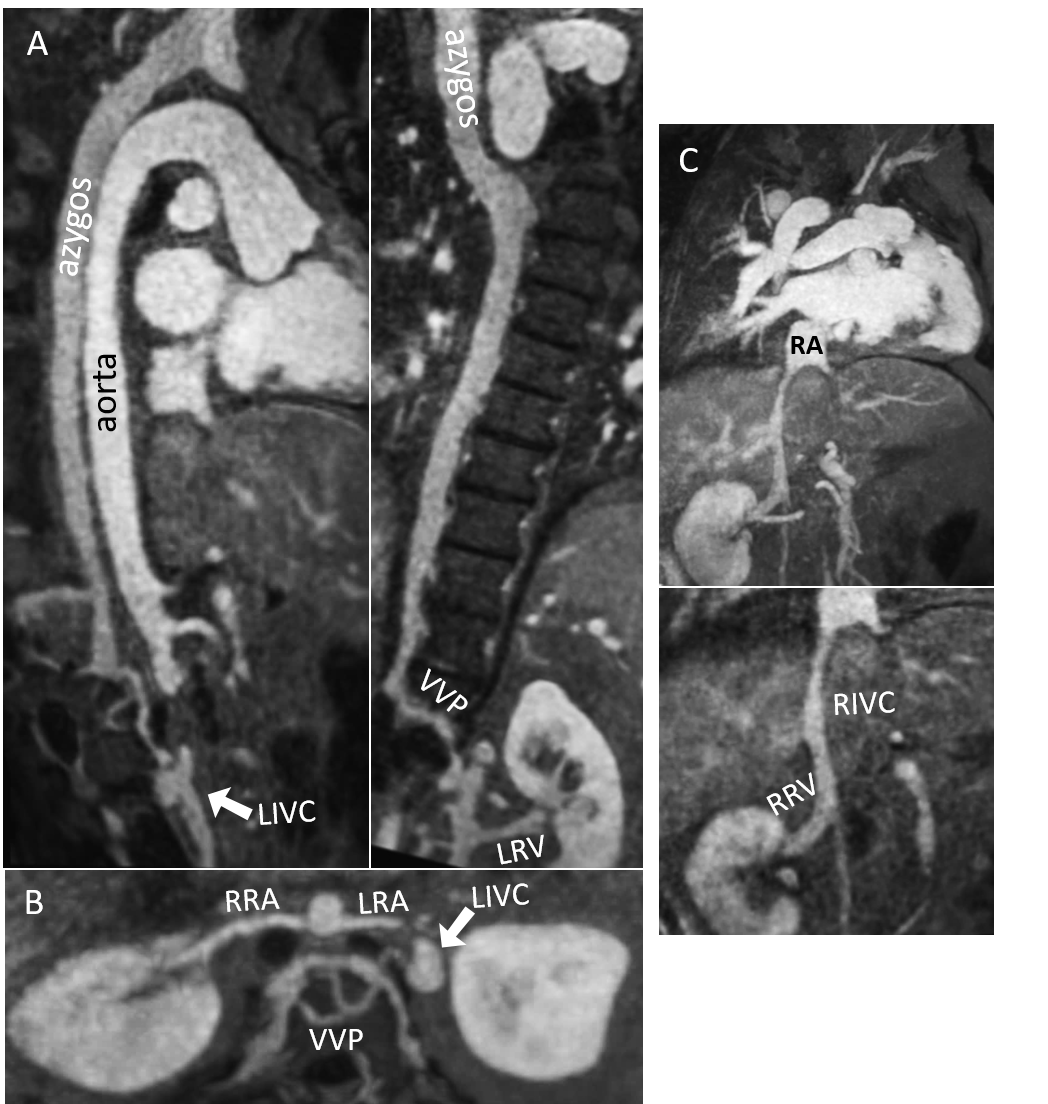

Fig 2- Demonstration of dual inferior venal cava anatomy using image-based navigator (iNAV) gadolinium enhanced MRA. (A) The azygos continuation joins the vertebral venous plexus (VVP), from which the left inferior vena cava (LIVC) originates. There is drainage of the left renal vein (LRV) into the LIVC. Inset- there is normal connection of the hemiazygos to the azygos vein. (B) Axial maximal intensity projection reformats demonstrate the relationship between the left renal artery (LRA), right renal artery (RRA), LIVC, and VVP. (C) The right renal vein (RRV) is a branch of the right inferior vena cava (RIVC), which terminates into the right atrium (RA). Notice continuation of the RIVC inferior to the origin of the RRV.